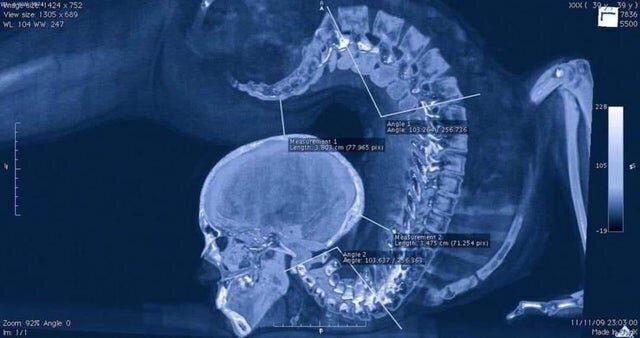

11. Обратите внимание на позвоночник: рентген гимнастки в прогибе